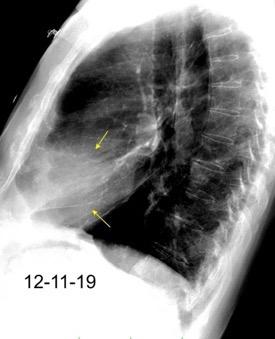

Neumonía a neumococos base izda. con derrame que aumenta.

Broncograma en lateral y en US.

(36-66% en ingresados)